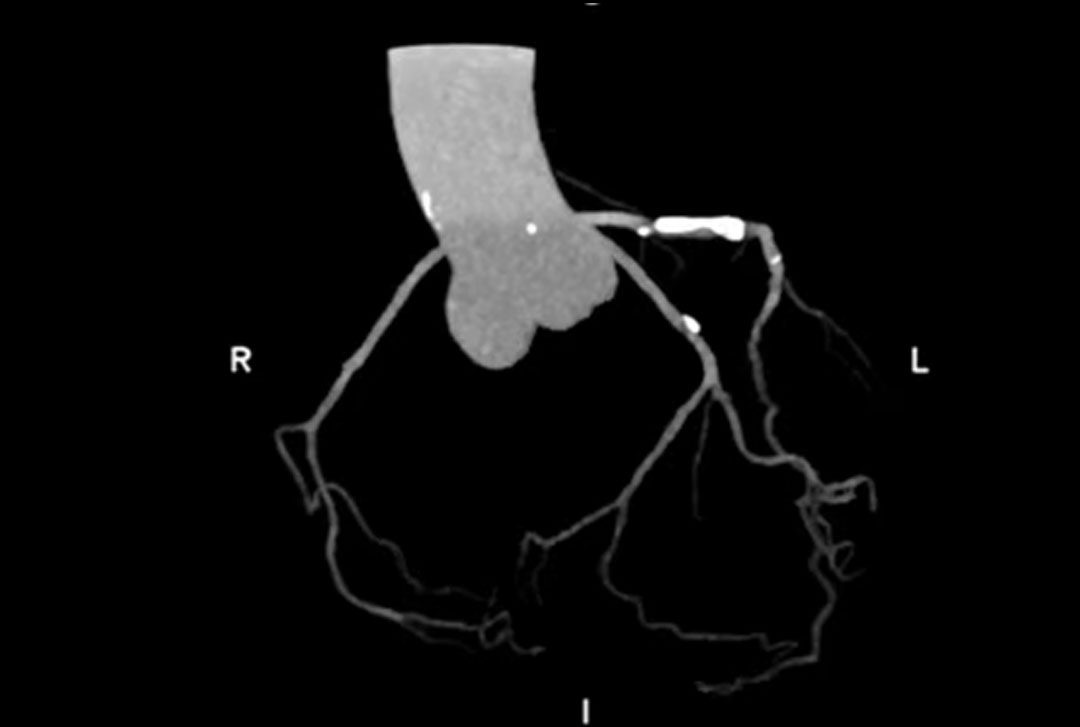

(患者的冠状动脉CTA图像)

在一次上海百汇医院心内科门诊就医中发现,他的心脏动脉已经发生明显的动脉硬化。我们的医生及时介入前期治疗,针对他的身体状况,个性化定制了诊疗方案:以预防性药物降脂降压,并配合改善生活方式的干预建议,如:减少了高脂肪和高盐的食物摄入,戒烟、戒酒,适当增加运动量,并定期监测血压、血脂水平等,管理自己的病情。在之后的复诊中,他的健康状况得到了明显得改善。